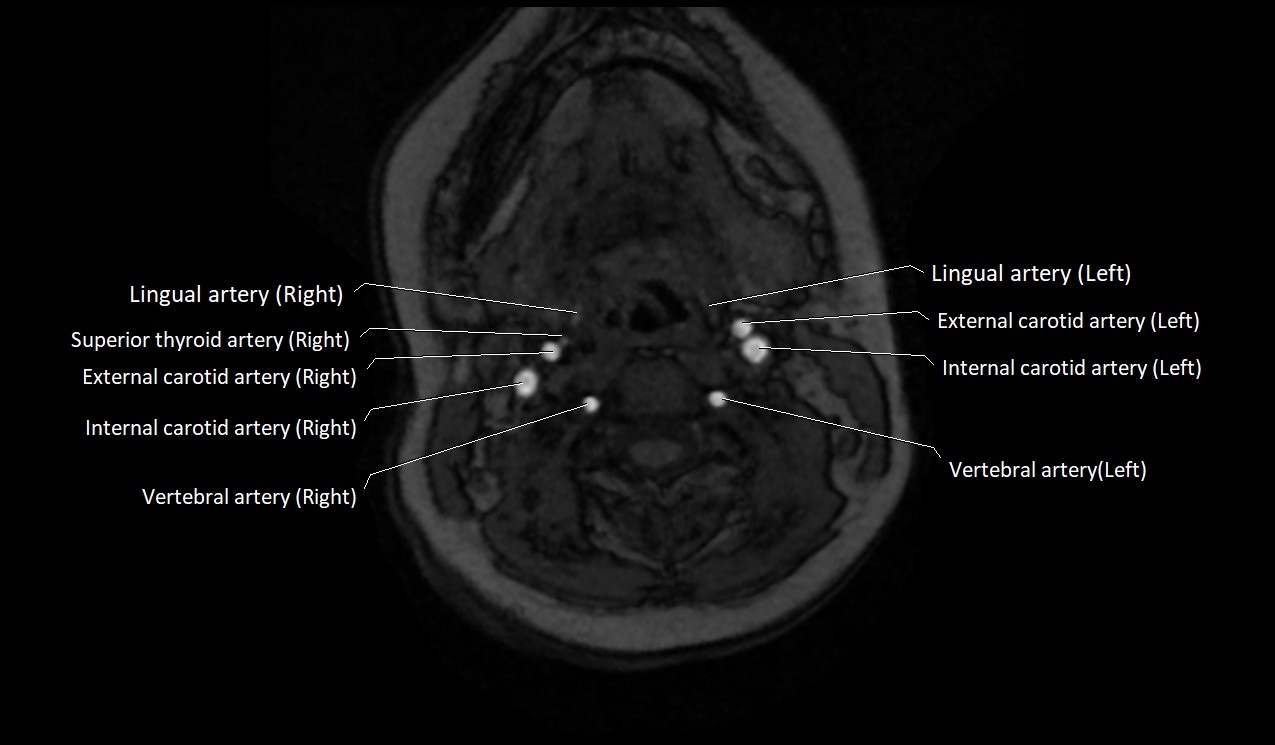

CT image

image